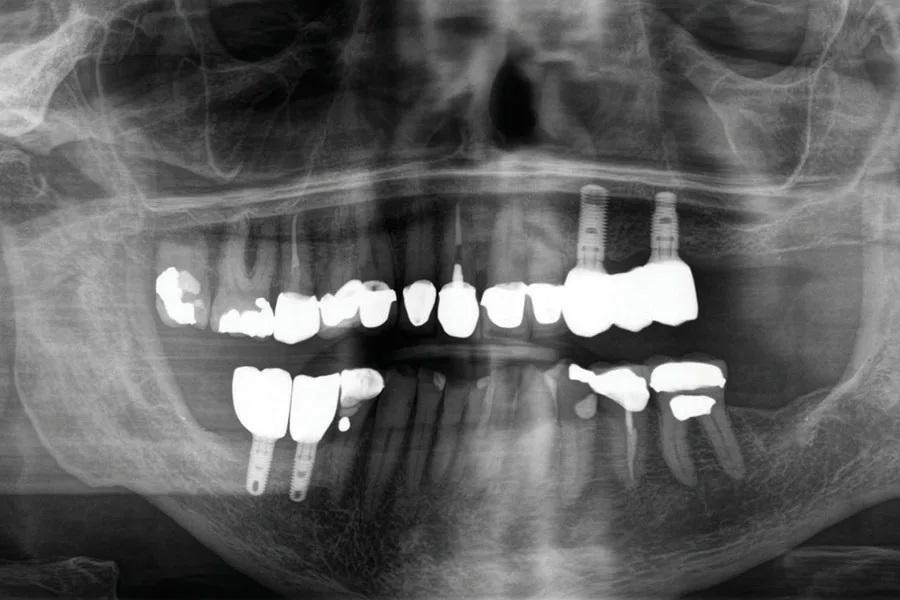

Панорамный рентгеновский снимок, полученный на основе КЛКТ, показал скошенный вертикальный дефицит костной ткани в правом боковом отделе нижней челюсти с недостаточной высотой кости для установки дентальных имплантатов выше нижнего альвеолярного нерва (Фото 1). КЛКТ левого верхнечелюстного квадранта выявила разрушенный левый клык с достаточным объемом кости для установки имплантатов в области клыка и второго премоляра.

Фото 1. Предоперационный панорамный рентгеновский снимок, полученный на основе КЛКТ, демонстрирующий вертикальную атрофию кости в правом боковом отделе нижней челюсти.